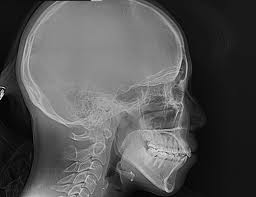

X-Ray กระโหลกศรีษะเพื่อการตรวจความผิดปกติของช่องปาก กระโหลกศรีษะ ขากรรไกร ใบหน้า เพื่อใช้ประกอบการจัดฟันและการรักษาอื่นๆตามต้องการ

X-Ray กระโหลกศรีษะเพื่อการจัดฟัน และการตรวจช่องปากทั้งฟัน กระดูกขากรรไกร ข้อต่อขากรรไกร โพรงอากาศใต้โหนกแก้ม โพรงจมูก และกระดูกคอ เพื่อใช้ประกอบการจัดฟันและการรักษาอื่นๆที่ต้องการ